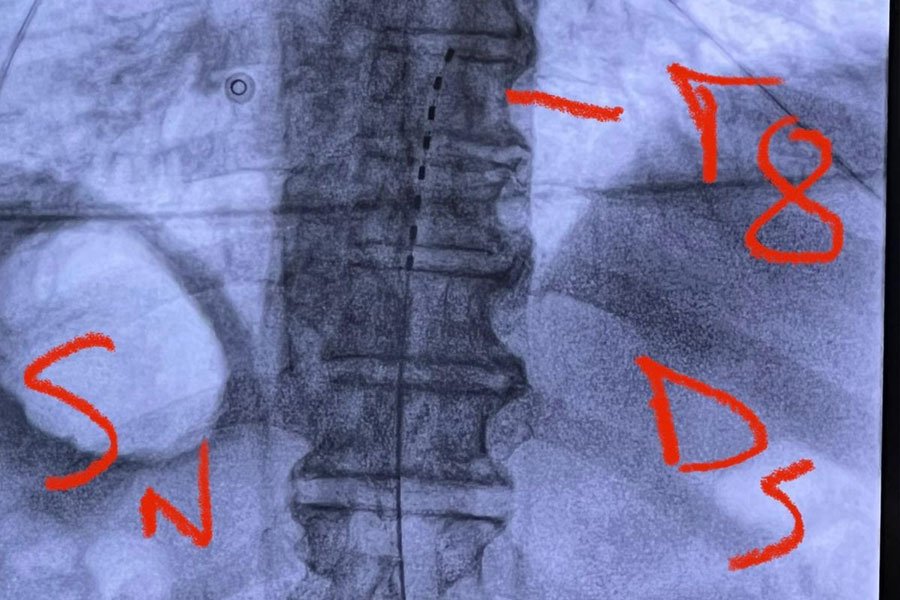

Gli elettrodi vengono posizionati a livello dello spazio epidurale attraverso un’incisione percutanea in anestesia locale, quindi, collegati al generatore di impulsi che viene posizionato dentro una tasca sottocutanea in regione sovraglutea.

• Una prima fase “trial” che consiste nell’impianto del solo elettrodo midollare per testarne la sua efficacia nel controllo del dolore.

• Nella seconda fase, una volta appurata la sua efficacia antalgica a distanza di qualche settimana, il generatore viene impiantato in maniera definitiva in sede sottocutanea.